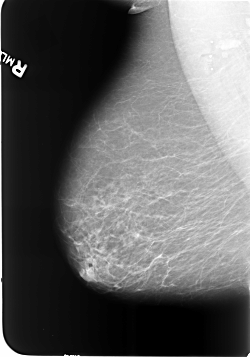

B_3473_1.RIGHT_MLO

RIGHT_MLO LINES 5712 PIXELS_PER_LINE 3992 BITS_PER_PIXEL 12 RESOLUTION 50 NON_OVERLAY